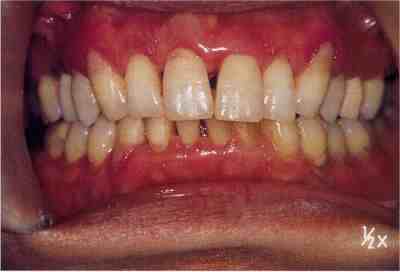

Sleep splint(口腔内装具)を装着した状態

装具装着前